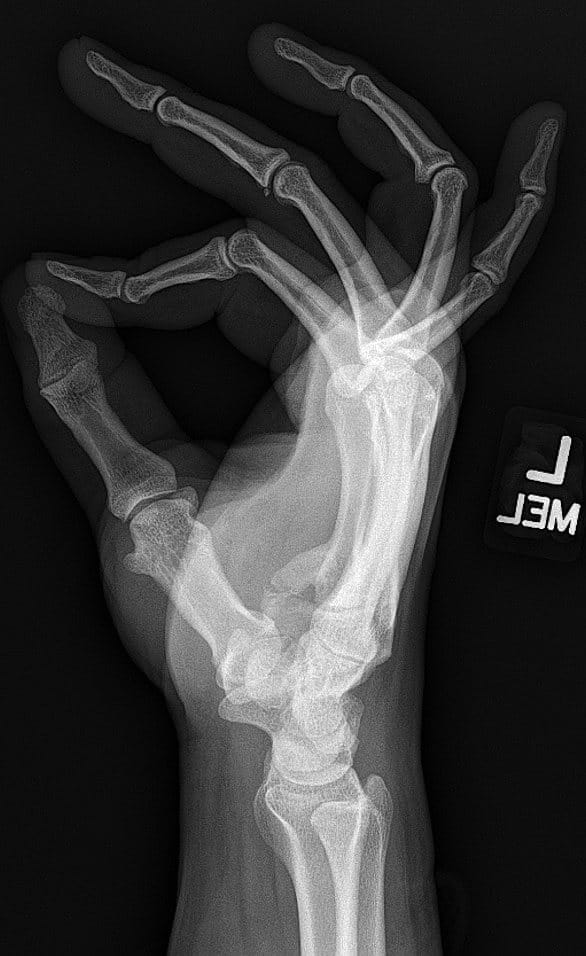

Lateral radiograph of hand demonstrating heterotopic bone extending from the base of the 5th metacarpal towards the hook of hamate displacing the ulnar nerve in a volar directionLateral radiograph of hand demonstrating heterotopic bone extending from the base of the 5th metacarpal towards the hook of hamate displacing the ulnar nerve in a volar direction.